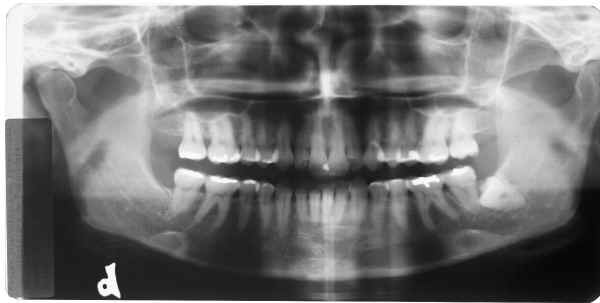

Todas as radiografias foram alteradas a partir da seguinte original:

Radiografia original sem retoques